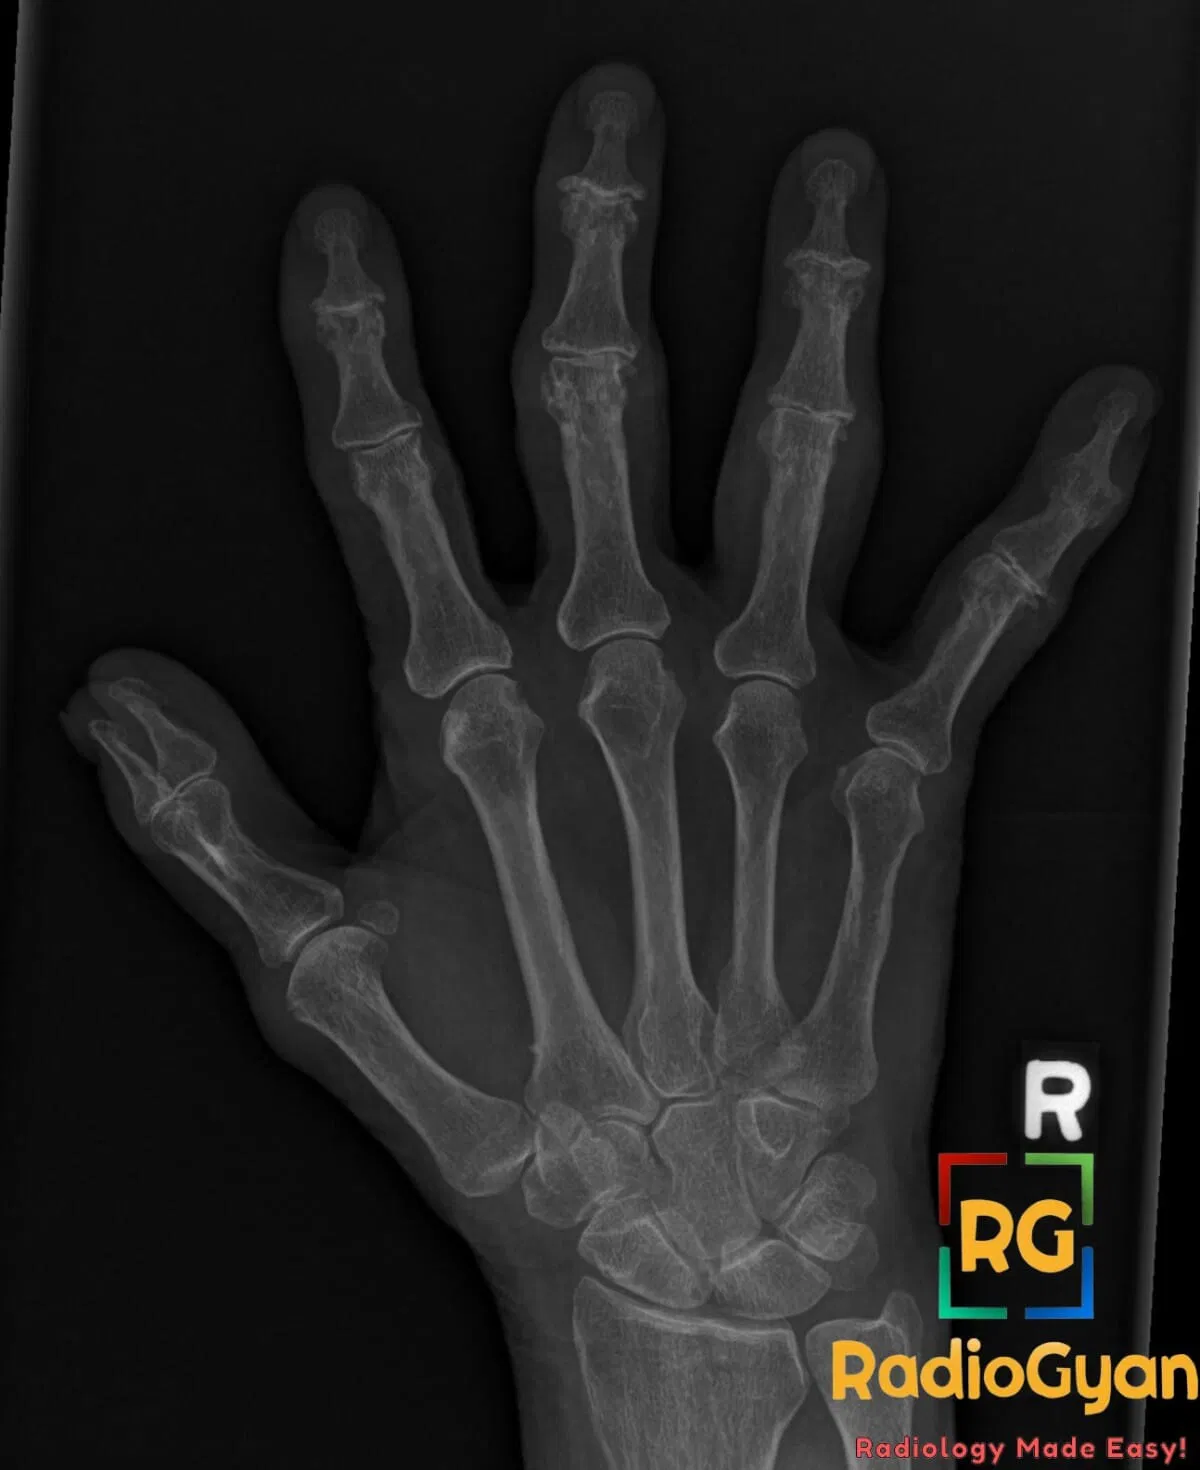

The gullwing appearance is caused by erosive changes in the distal interphalangeal (DIP) joints characterized by central erosions with surrounding subchondral sclerosis and marginal osteophyte formation. This is a hallmark radiographic feature of erosive osteoarthritis, an inflammatory subtype of osteoarthritis affecting the DIP joints, producing pain, stiffness, and joint deformity.

The term “gullwing” derives from the radiographic outline of the joint erosions and osteophytes resembling the wings of a seagull in flightโtwo symmetrical concave erosions centrally with sclerotic margins on either side, creating a bilobed shape similar to a gull’s wings.

The gullwing appearance develops due to an initial central subchondral bone erosion in the DIP joint caused by inflammation and cartilage loss. This central erosion is flanked by new bone formation at the joint margins (osteophytes) and reactive subchondral sclerosis. The combination of central erosions and peripheral bone proliferation leads to the characteristic bilobed radiographic contour.

Alternative names: Seagull erosions, sawtooth appearance